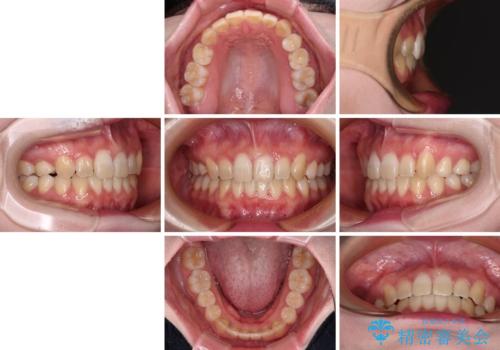

上顎に乳歯が左右1本ずつ残っていたため、若干咬み合わせに不具合が残りましたが、強い咬合力の原因であったディープバイトをしっかりと改善することができました。

ディープバイトをインビザライン矯正で改善

インビザラインを用いて、前歯の叢生を解消するとともに、ディープバイトを改善していくこととしました。